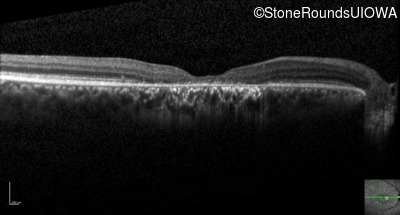

Optical Coherence Tomography - Right - 20/80 -1

Exemplar / OCT Stack

OCT Stack